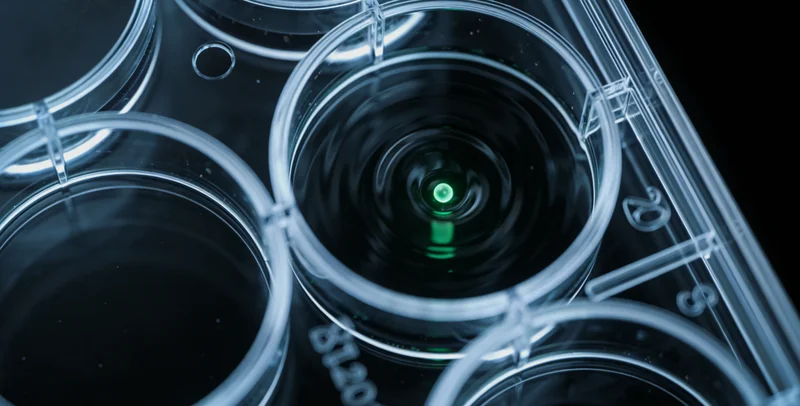

很多朋友每年都会参加单位或社区组织的常规体检,对血常规、B超等项目非常熟悉。这些检查固然重要,但它们更侧重于发现已经形成、甚至可能已经引起症状的病变。而全身MRI筛查是一种无辐射的影像学检查,它能对身体的主要部位(如大脑、颈胸腹盆腔、脊柱、关节等)进行一次“高清全景扫描”,在病灶还非常微小、甚至毫无症状的“超早期”阶段,就发现结构上的异常迹象。基因检测则是从另一个维度切入——解读每个人与生俱来的遗传密码,评估特定疾病(如多种遗传性肿瘤、心脑血管疾病、神经系统疾病等)的先天易感风险。两者结合,相当于既关注“地基蓝图”(基因),又定期“透视整屋”(结构),实现了对健康风险更立体的评估。

这个问题非常关键。B超和CT、X光主要看的是器官和组织的形态、密度变化,属于“看得见”的层面。基因检测看的则是细胞核内DNA序列上的信息,属于“看不见”的层面。简单来说,基因就像一本写满生命指令的“说明书”。基因检测技术,特别是高通量测序技术,可以读取这本说明书中的关键章节,看看是否存在一些“印刷错误”(基因突变)。这些“错误”可能使得某些维护身体正常运作的“防御机制”(如修复损伤、抑制异常增殖的基因)功能减弱,从而增加个体患上特定疾病的风险。这并非算命,而是基于现代分子生物学的风险评估。

整个流程可以概括为“咨询-取样-分析-解读”四个核心步骤。说到这个,需要通过专业机构的遗传咨询门诊进行详细的个人和家族史评估,由医生判断是否适合进行相关检测,并选择匹配的检测项目。第二步是取样,基因检测通常只需抽取少量静脉血或采集口腔黏膜细胞,取样过程简单快捷。全身MRI检查则需要前往配备有高场强磁共振设备的影像中心进行检查,过程无痛、无辐射。第三步,样本会被送往拥有专业资质的分子诊断实验室进行分析。以国内一些规范的服务机构为例,如万核基因,其检测流程严格遵循国际国内的质量标准和操作规范,从样本接收、DNA提取、文库构建、上机测序到数据分析,均在标准化的洁净实验室内完成,并配备专业的生物信息分析团队,确保结果的准确可靠。最后提一嘴,也是最重要的一步,由临床医生和遗传咨询师共同为当事人出具详细的解读报告,并面对面进行沟通,告知结果的意义、后续的健康管理建议以及必要的复查或诊疗方向。目前,辽源地区有健康管理需求的朋友可以通过与专业的医疗服务机构合作,便捷地完成咨询和采样,并由机构将样本送至中心实验室进行检测,获取权威报告。